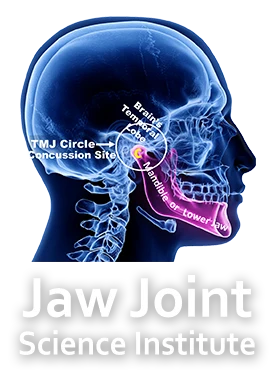

Society, at large, has not considered or examined the critical and inseparable relationships between the temporal brain, and the condyle of the lower jaw to the study and symptoms of concussions and TBIs. With the brain’s temporal lobe resting in juxtaposition to the condyle the vulnerability of concussive head impact is excessive and why the temporal lobe of the brain has become our center focus of the concussions

Impact with the testing headforms lacks the inclusion of this delicate anatomy, resulting in a widespread misdiagnosis of concussions, and TBIs, despite industry best efforts to protect the skull from impact forces using helmets. It is in fact, the lower jaw that traumatizes the brain through the TMJ!

The impact that causes a concussion can often fracture the delicate glenoid fossa bone of the Temporal Mandibular Joint that supports the base of the brain’s temporal lobe. Current concussion protocols do not address this fracture, often causing severe symptoms to persist. Treating this fracture will reduce or fully eliminate these symptoms.

Through the use of 3DCT scanning technology we have discovered fractures involving the temporal bones which support the temporal lobe of the brain, linking TBIs and the TMJ. These fractures are varied, involving the delicate structures of the TMJ and have been directly linked to the symptoms of TBIs, concussions and temporal mandibular disorders (TMDs).